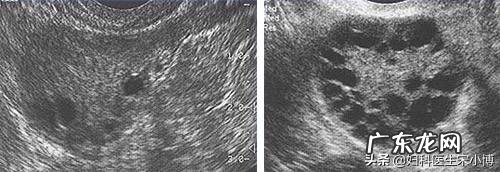

多囊卵巢和多囊卵巢综合征区别多囊卵巢是指超声显示一侧或两侧卵巢各有12个或以上直径在2-9mm小卵泡或者/和是卵巢体积>10ml,它是一种征象 。而多囊卵巢综合征是妇科常见的一种内分泌疾病 。